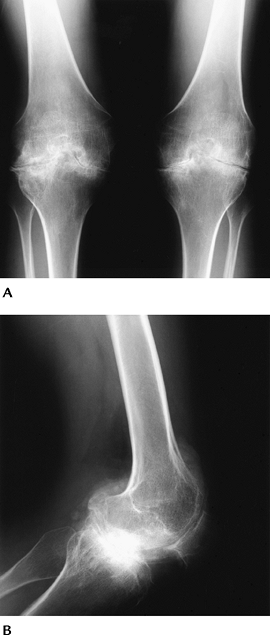

![]() |

FIGURE 5-62 Blount disease. AP radiographs of both knees (A,B) showing metaphyseal and epiphyseal deformities medially with genu varum deformities of the knees.

|